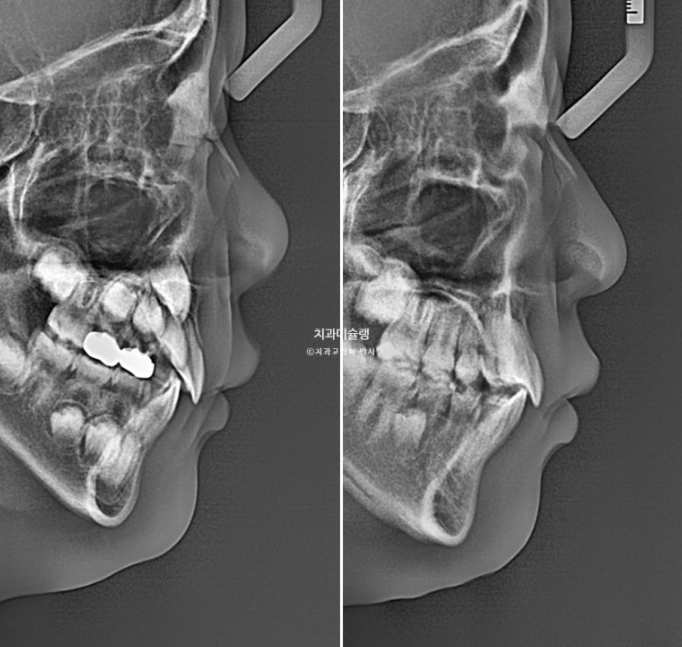

이제 안모비교 보겠습니다.

23.10~25.11

작았던 아래턱이 성장하면서 안모가 좋아졌습니다.

잇몸노출량도 줄고 뻗처있던 앞니 각도도 좋아졌습니다.

엑스레이 비교를 해보면 이러합니다.

치아 뿌리가 잘 자라고 있습니다.

치근평행도는 좋습니다.